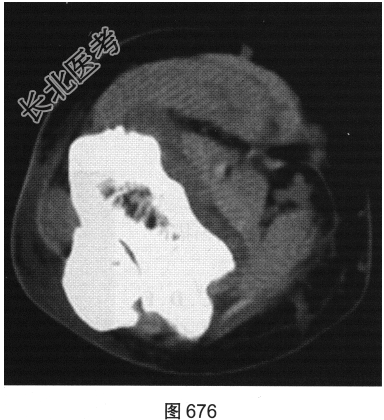

- [材料题] 患者女性,62岁,右侧肘关节肿胀、疼痛1年余。肘关节正侧位X线片及CT检查见图673~图676。

- 简答题1、请对该患者影像征象进行描述。

- 简答题2、根据题干中患者的临床表现及影像特征,请问该患者应首先考虑哪种疾病?